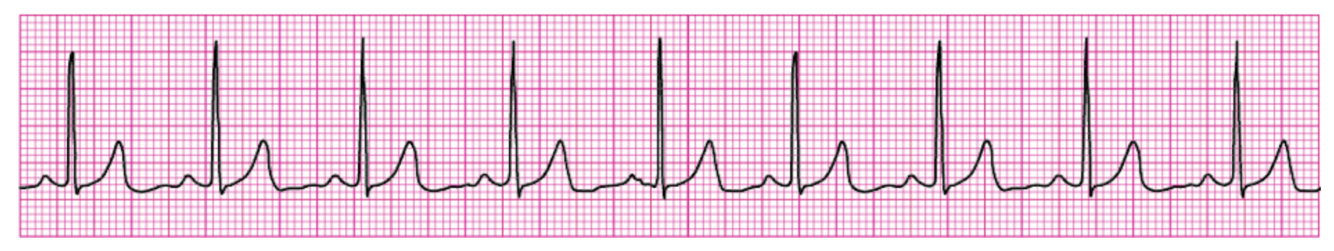

What is this rhythm?

Normal sinus rhythm

Q

You see this rhythm, but there is no pulse, what’s the issue?

Pulseless electrical activity (PEA).

Sinus Tachycardia. To estimate the HR, divide 300 by the number of big boxes between QRS complexes.